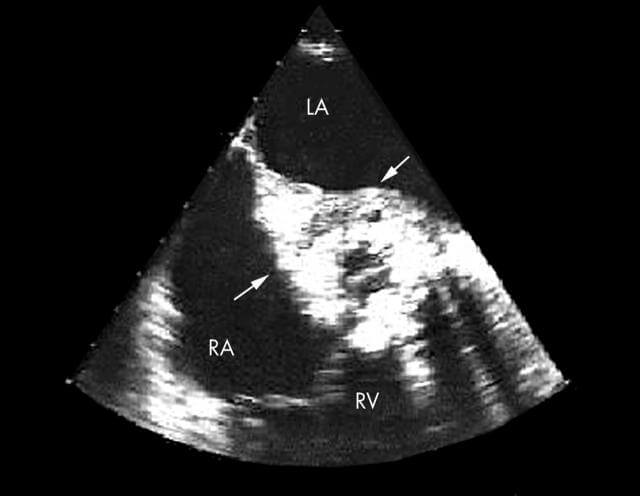

No diagnóstico ecocardiográfico da endocardite infecciosa, certos achados são considerados indicativos clássicos da doença. Entre eles, destacam-se as vegetações, que apresentam-se como massas móveis e ecodensas aderidas às válvulas cardíacas ou outras superfícies endocárdicas, frequentemente associadas a áreas de fluxo turbulento.

Além disso, a presença de abscessos perivalvulares constitui um importante sinal de comprometimento local avançado. Tais achados caracterizam-se por coleções anecoicas ou hipoecoicas adjacentes às válvulas, muitas vezes detectadas com maior precisão pelo ecocardiograma transesofágico.